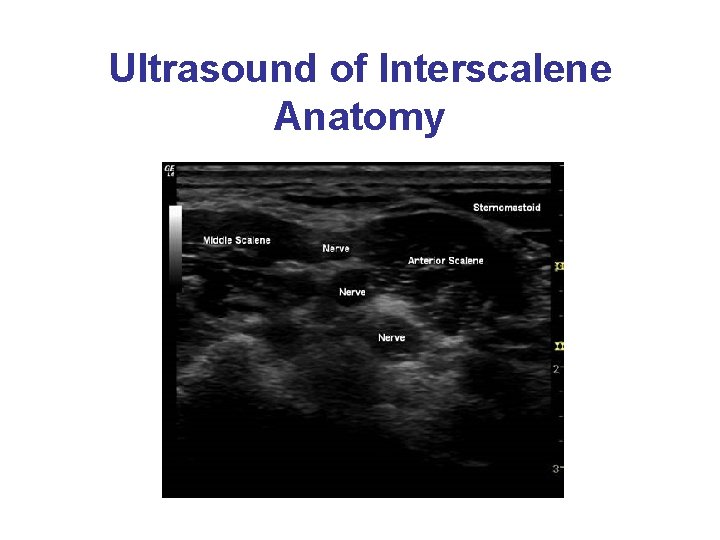

Ultrasound of Interscalene Anatomy